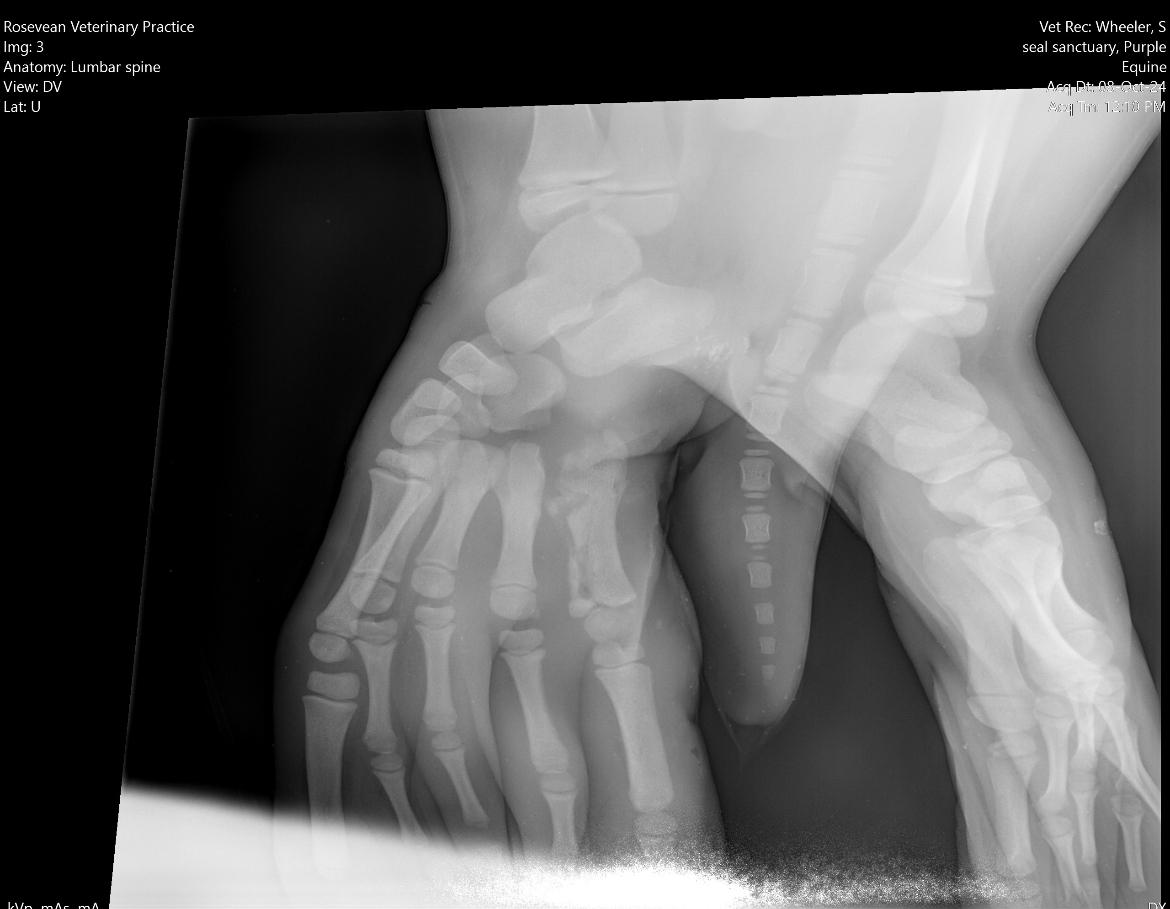

Leaf Cutter was rescued from Carbis Bay by British Divers Marine Life Rescue malnourished and hypoglaecemic, with an obvious wound to her front flipper. After four days at their hospital she was brought to us and after examination by our vets they confirmed the suspicion of potential osteomyelitis in her front right flipper with a persistent puncture wound that was not healing.

The vets put her on a course of treatment but said to come back to them if the swelling was not going down.

Unfortunately, this was the case, and we therefore booked in for her to get an X-Ray. This showed us that she has a fractured metacarpal. After some further discussion with the vets, we decided to proceed with an operation to give her the best chance of survival.